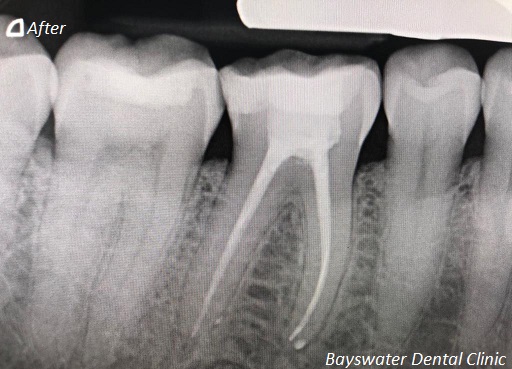

Root canal treatment on three rooted tooth! which had 4 canals!